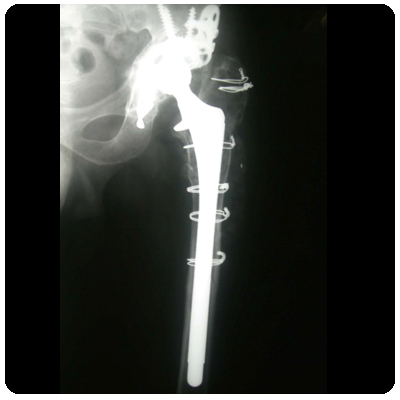

Upload Date: January 23, 2019 Full Size Image Dimensions: 400 × 400 Image Parent Post: Αναθεώρηση Αρθροπλαστικής Ισχίου σε 1 ή 2 στάδια

Ακτινογραφία με κοτύλη-κλωβό